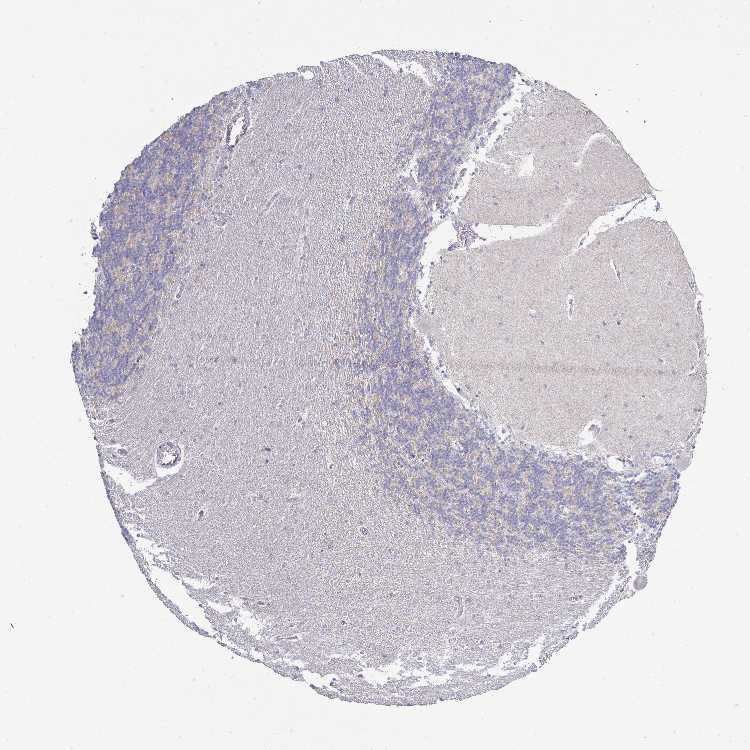

CEREBELLUM - Antibody stainingi

Antibody staining in the annotated cell types in the current human tissue is reported as not detected, low, medium, or high, based on conventional immunohistochemistry profiling in selected tissues. This score is based on the combination of the staining intensity and fraction of stained cells.

Each image is clickable and will lead to virtual microscopy that enables deeper exploration of all samples and also displays staining intensity scores, fraction scores and subcellular localization as well as patient and tissue information for each sample.

Antibody HPA001383Antibody CAB000043Antibody CAB020416Antibody CAB062555

Purkinje cells MediumNot detectedNot detectedNot detected

Cells in granular layer Not detectedNot detectedNot detectedNot detected

Cells in molecular layer LowNot detectedNot detectedNot detected